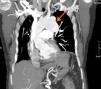

Neste contexto, foram requisitados vários outros exames complementares de diagnóstico. O ecocardiograma transtorácico revelou aspetos compatíveis com pericardite constritiva – espessamento e ecogenecidade aumentada do pericárdio e importante variação respiratória da onda E no fluxo transmitral (Figura 1A e B) e fração de ejeção ligeiramente deprimida.

Realizou um cateterismo cardíaco esquerdo e direito, tendo sido excluídas lesões angiograficamente significativas nas artérias coronárias e confirmado o diagnóstico de pericardite constritiva no estudo hemodinâmico (com as típicas curvas de pressão ventricular em dip-and-plateau e equalização das pressões telediastólicas). Na aortografia foi documentada dilatação da aorta torácica descendente. Para melhor caracterização da aorta, foi realizado uma angio-TC de tórax, que revelou um volumoso aneurisma saculiforme, parcialmente trombosado, com origem na aorta torácica descendente, imediatamente distal à emergência da artéria subclávia esquerda, com 87 x 61mm de diâmetro (Figura 2); não se observou calcificação do pericárdio.